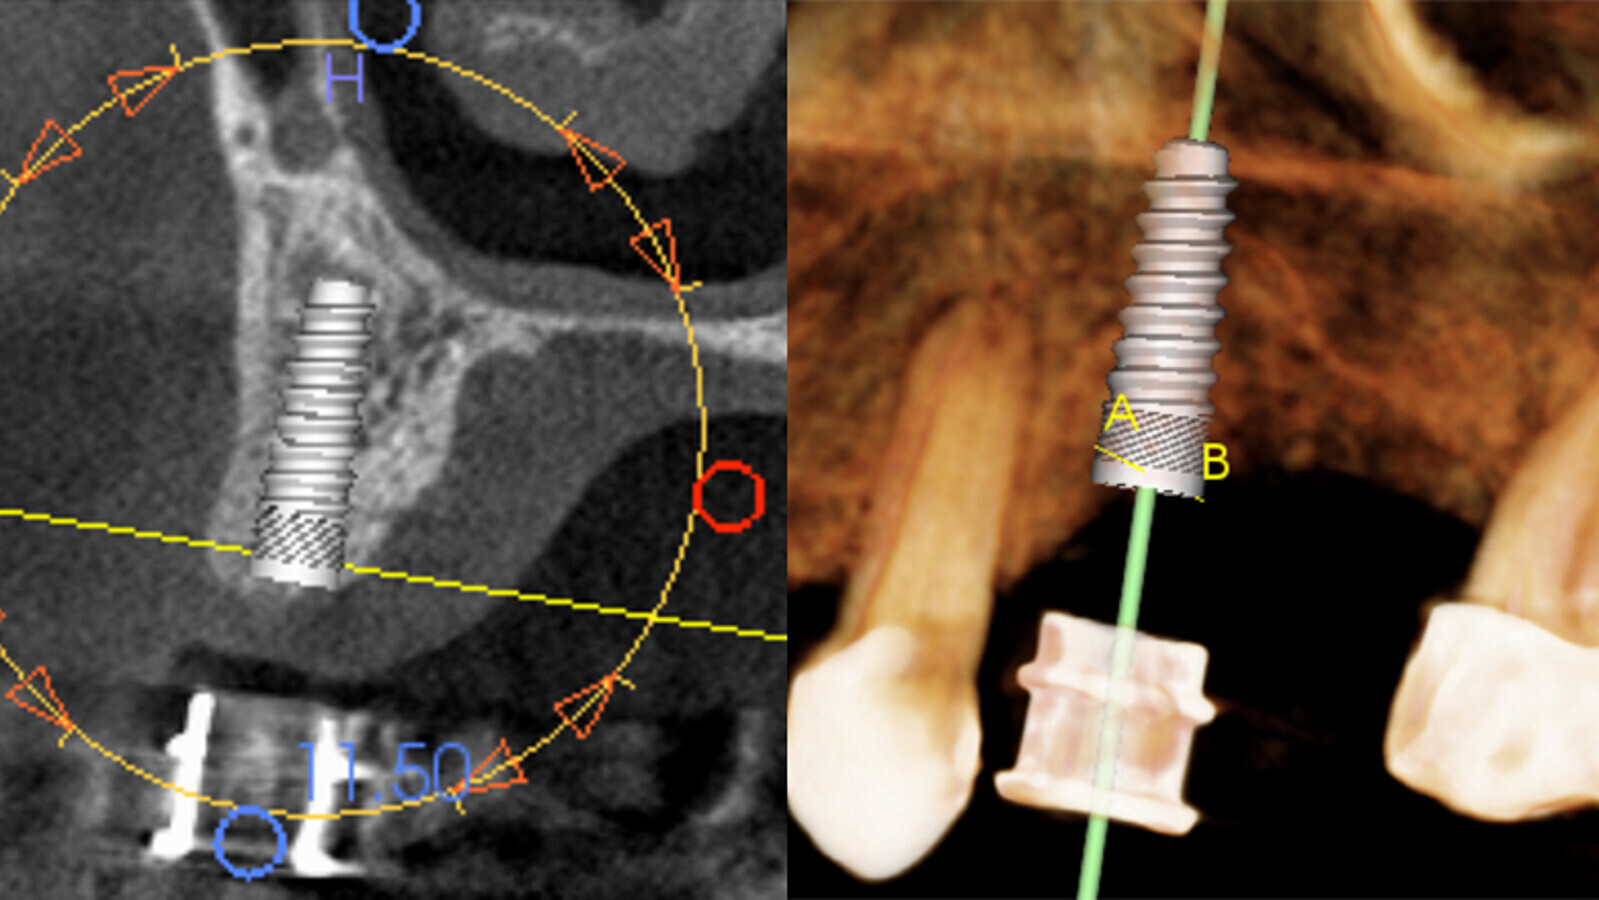

Figura 2. Se realiza una tomografía Cone Beam con la guía puesta en boca del paciente.

Figura 3. Ya con la tomografía Cone Beam, se procede a medir altura y espesor óseo.

Figuras 4a, 4b. Con la información proporcionada por la tomografía Cone Beam, realizamos la planificación virtual del implante, angulación e inserción ósea, utilizando el software del propio tomógrafo.

Figuras 7a, 7b PRE Qx. En la tomografía Cone Beam pre-quirúrgica se observa la planificación digital del implante en cuanto a su angulación, dirección y posicionamiento.